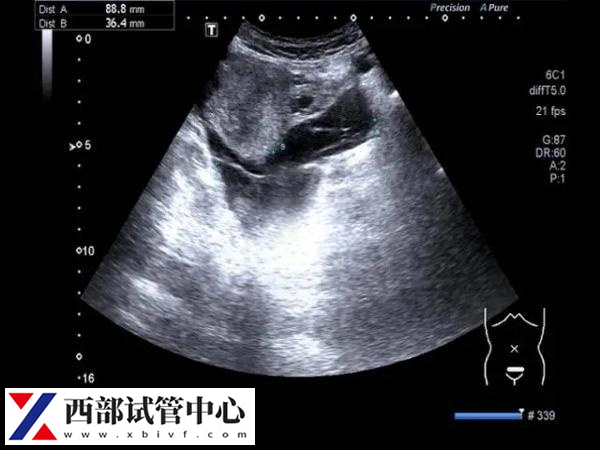

卵黄囊通常在怀孕的第5到第10周之间可见。卵黄囊是妊娠囊内超声能发现的第一个解剖结构,通常在孕早期就会出现。卵黄囊的形态呈球形,囊壁薄,中央为无回声。在怀孕的第7周时,卵黄囊的最大直径可达5mm,而到了第10周以后,卵黄囊会逐渐缩小,直到孕12周后完全消失。

而在囊胚移植手术后,通常可以在移植后约35天看到卵黄囊。但要注意,如果是在自然妊娠中,孕7到11周之间超声检查中未显示卵黄囊或胚胎,应考虑发育异常的可能性。